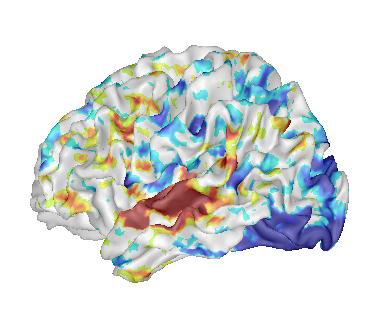

Fusion between an anatomical volume and an activation map

Load:

T1 MRI:

data_for_anatomist/subject01/subject01.niiActivation map:

data_for_anatomist/subject01/Audio-Video_T_map.nii

Fusion the 2 images. Note that they are not well superimposed because they are not in the same referential. But they are in Nifti format and contain information about a transformation to the referential Talairach-MNI Template-SPM.

For each volume, right-click Referential => Load information from file header.

Look at the fusion, the 2 images are now well superimposed.

Change the point of view by changing the referential of the window: click on the colored bar at the top of the window and choose Talairach-MNI Template-SPM. Notice the change of orientation.

Fusion between an activation map and a T1 MRI¶